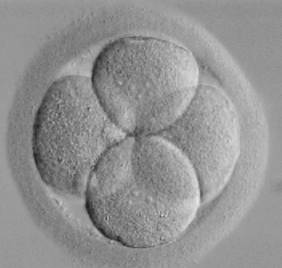

írta:bridget0801Kerdesem az lenne,hogy nem baj,hogy 4sejtesen kaptam visszabar az enyem mintha mar haladt volna a 6sejt fele mert kis buborekok voltak a 4nagy mellett